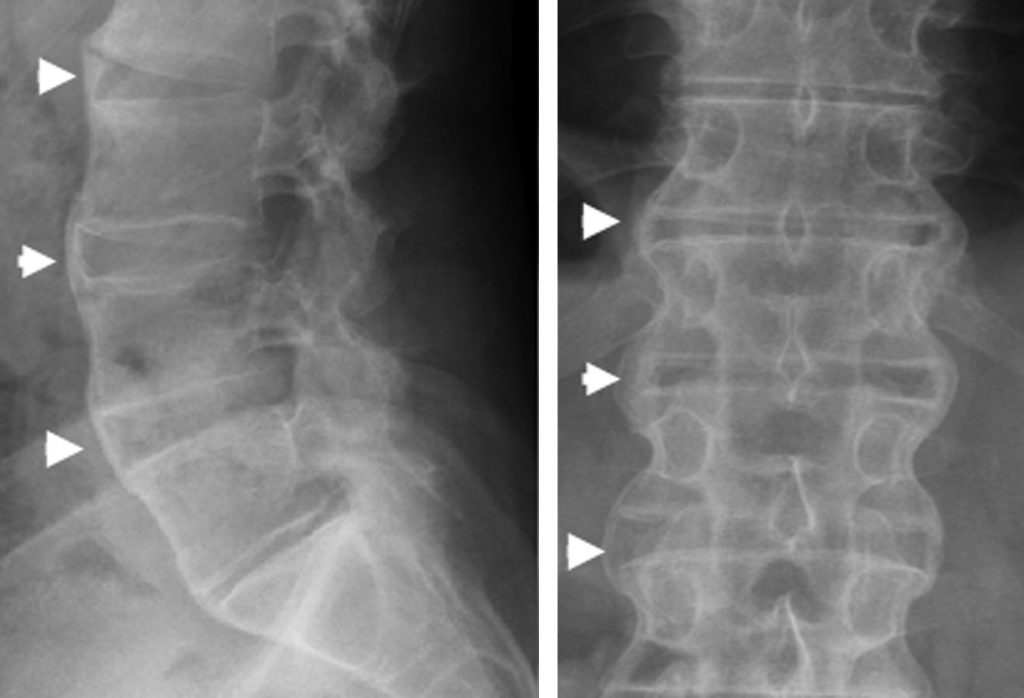

Fig. 84.1 Spondylarthrite ankylosante en phase avancée.

Radiographies de face et de profil du rachis lombaire avec syndesmophytes réalisant des ponts osseux entre les corps vertébraux (têtes de flèche).

Source : CERF, CNEBMN, 2022.